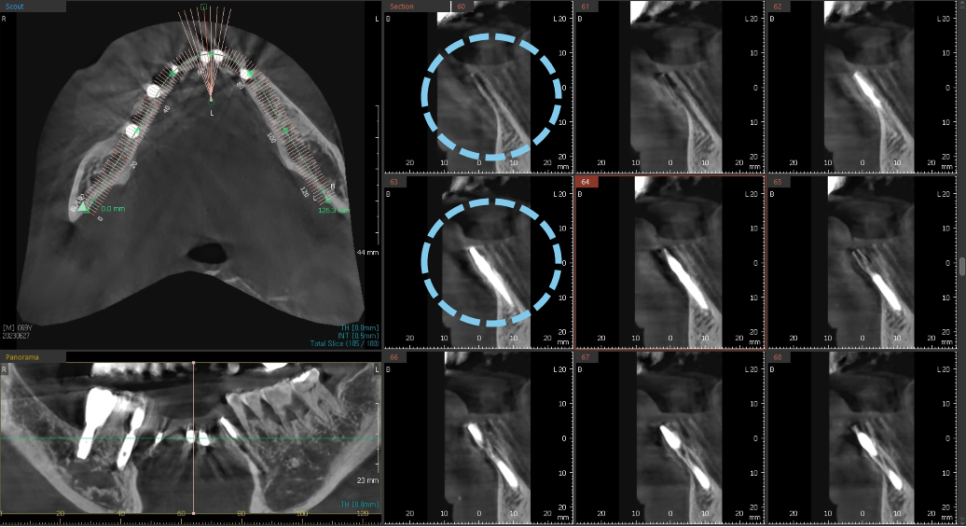

발치 후 염증으로 인해 대다수 소실된 뼈 부분을 보면

아주 얇고 경사가 심한 포인트라

임플란트를 심을 길을 내는 것도

아주아주 어려운 일입니다.

발치와 동시에 식립하는 임플란트는 정밀함을 요합니다.

앞니의 경우라면 더더욱 세심한 분석과 위치 선정이 중요하고

통상적으로 염증이 많은 부분을 깨끗하게 제거 한 뒤

뼈이식과 함께 임플란트를 하는

앞니 임플란트 술식은 매우 고난이도에 속합니다.

노란색으로 표시된 곡선의 움푹 들어간 부분이

실제로 수술시에 육안으로 잘 보이지 않기 때문에

손으로 만져보면서 조심스럽게 진행해야합니다.

또 너무 뒷쪽으로 식립하게 되는 경우

파란색 선 뒷쪽에 위치한 혀쪽의 설동맥과 가까워지게 되는데

설동맥을 건드린 경우는 대량의 출혈이 일어나게 됩니다.